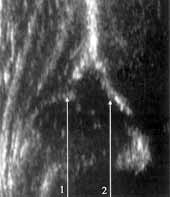

Нижний край подвздошной кости — первая и наиболее важная координата измерений. Он может отсутствовать лишь на сонограммах с децентрироваными суставами, когда датчик в поисках сместившейся головки бедренной кости покидает среднюю часть вертлужной впадины. При обследовании децентрированных суставов принципиально важны не измерения углов, а направление смещения хрящевой части: краниально (тип III) или каудально (тип IV) (Рис. 2).

Нижний край подвздошной кости — первая и наиболее важная координата измерений.

Он может отсутствовать лишь на сонограммах с децентрироваными суставами, когда

датчик в поисках сместившейся головки бедренной кости покидает среднюю часть

вертлужной впадины. При обследовании децентрированных суставов принципиально

важны не измерения углов, а направление смещения хрящевой части: краниально

(тип III) или каудально (тип IV) (Рис. 2).